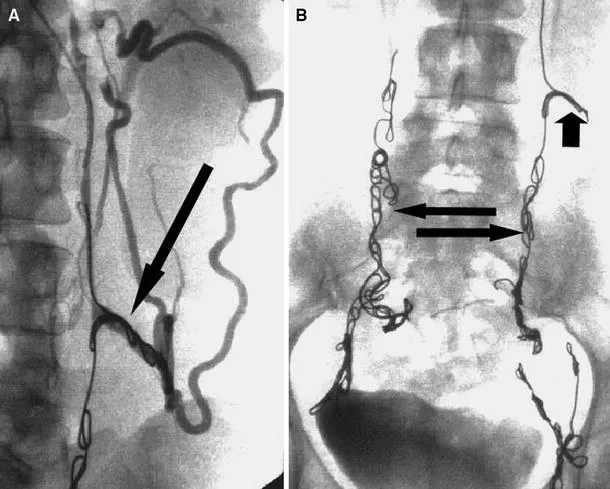

超声引导下经腔穿支静脉闭塞 (TRansluminal Occlusion of Perforators, TRLOP) 手术。

在穿支静脉反流 (PVR) 的治疗中,一般采用介入放射学方法进行治疗。颈静脉入路较为理想,因为待治疗的静脉与右侧颈内静脉呈相对直线,但也有人倾向于经股静脉入路。研究表明,虽然性腺静脉可能受累,但在超过95%的病例中,至少一条髂内静脉或其属支是问题的主要原因。因此,除治疗性腺静脉外,消融髂内静脉及其属支通常是必不可少的。

一旦在X线控制下对目标静脉进行了插管,最广泛使用的治疗方法是栓塞弹簧圈或栓塞剂。许多工作人员首先将泡沫硬化剂注入盆腔静脉曲张处,然后将弹簧圈或栓塞剂注入静脉主干部分。其他工作人员则主张使用球囊隔离功能不全的盆腔静脉,然后向远端注入泡沫硬化剂。然而,由于静脉的大小和静脉壁的厚度,除非在泡沫硬化剂治疗的近端使用栓塞装置,否则这种方法不太可能获得良好的长期结果。

显示腿部近端静脉和右髂内静脉分支之间的沟通。

(A)左卵巢静脉栓塞(短箭头)。反流扩张的髂内静脉属支(长箭头)。(B)栓塞的左髂内静脉血流停止(箭头)。

(A)迷走左腰静脉线圈(箭头)。如果没有选择性栓塞,这将继续充盈左卵巢静脉,并导致持续的反流。(B)栓塞后的左右卵巢静脉(长箭头)和迷走的左腰静脉(短箭头)。